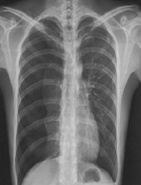

病史:男性,65岁,活动后胸闷6个月。既往高血压病史15年。诊断:

○ 靴型心

○ 梨形心

○ 普大型心脏

○ 正常心脏

○ 以上均不是